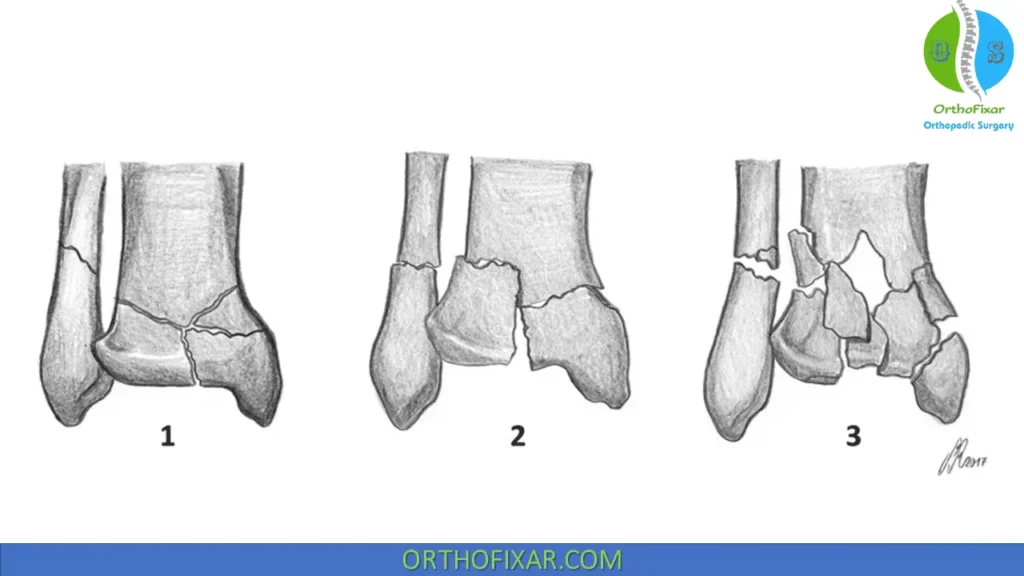

Ruedi and Allgower Classification of Pilon Fractures:

| Classification | Description |

|---|---|

| Type 1 | Cleavage fracture with no major articular disruption |

| Type 2 | Fracture dislocation with major articular surface disruption, without comminution |

| Type 3 | Major articular disruption with impacted and comminuted fracture |